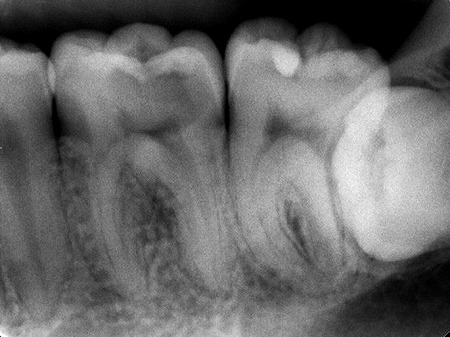

これは、3日程前に来られたある患者様のレントゲン写真です。歯がズキズキするという事で神経を殺す事になってしまいました。原因は下の写真の黄色の丸の部分の虫歯ですが、上から見てもプラスチックが詰めてあるだけで虫歯になっている様子はなかったのです。しかし麻酔してプラスチックを外すとボロボロになつていました。

赤い丸の部分はこれから虫歯が進行して行こうとしている所で、同じくプラスチックの詰め物がしてあります。